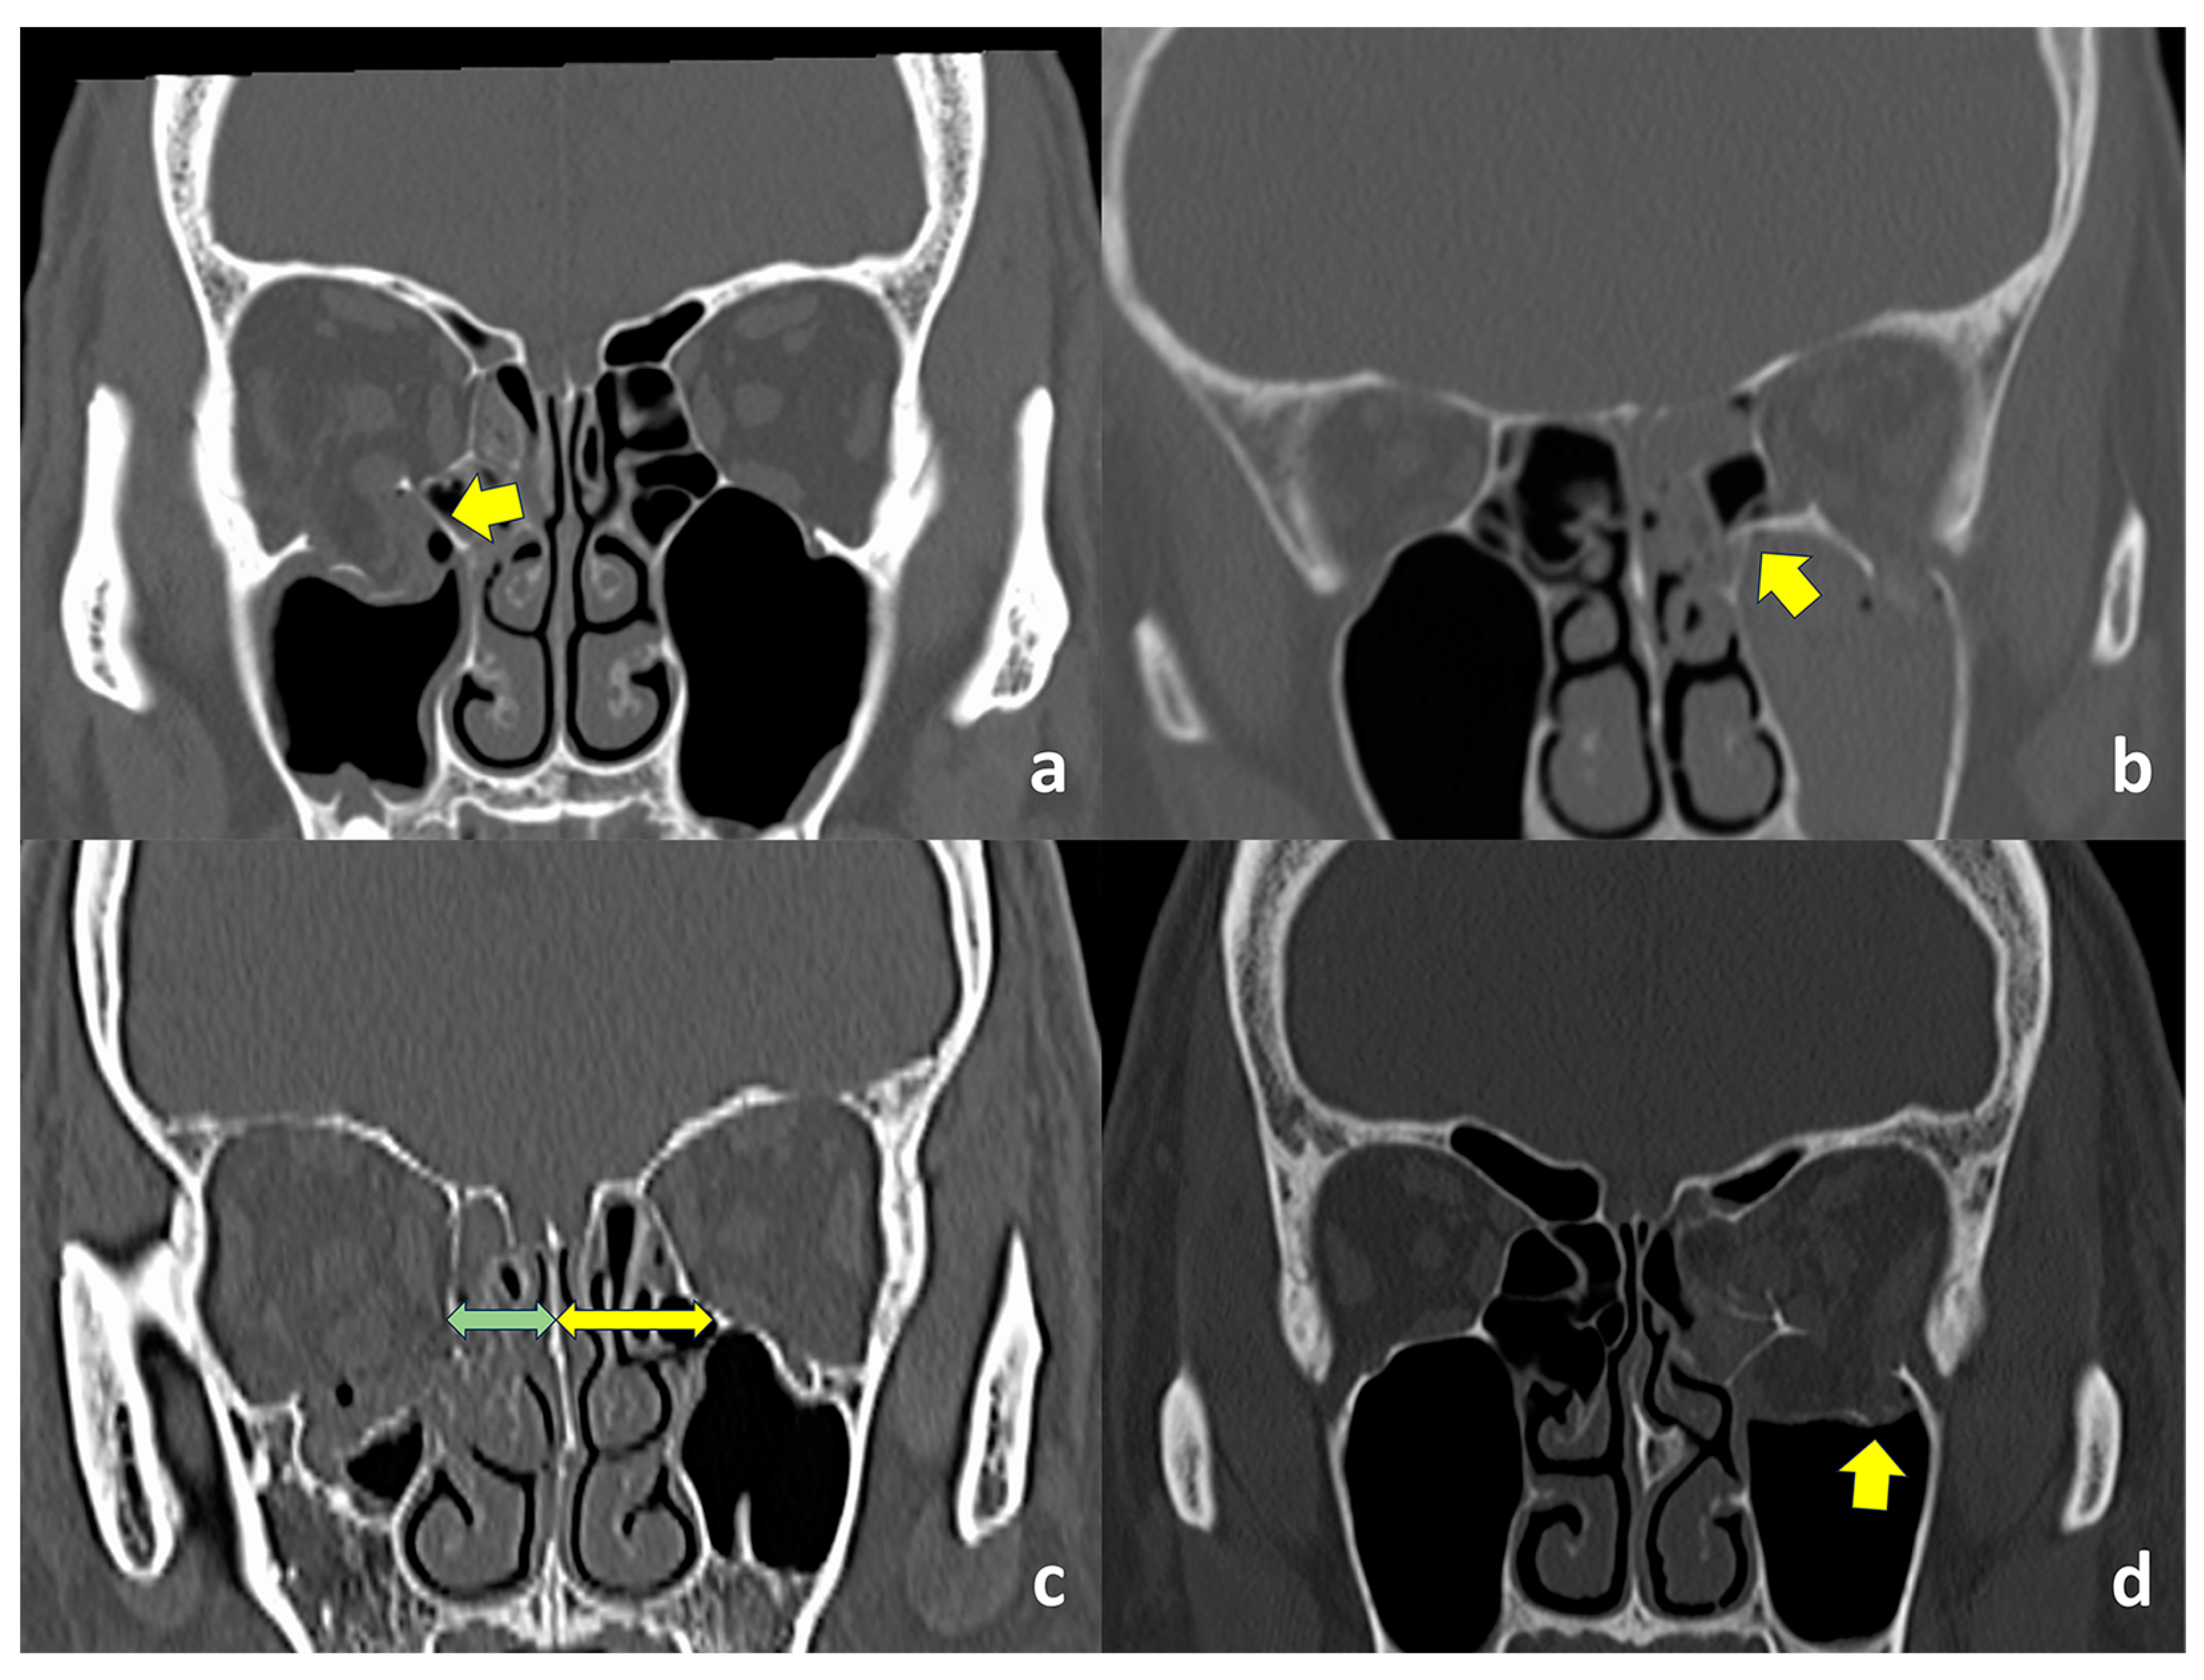

Axial and coronal CT images with bone and soft tissue window algorithms were obtained from all patients. Inferomedial strut fractures were diagnosed in cases with apparent strut fractures shown on coronal CT images (Figure 1a,b) or when the distance from the junction between the orbital floor and medial orbital wall and nasal septum was apparently shorter on the affected side (Figure 1c). Orbital fracture patterns, sites, entrapped orbital soft tissues in cases with trapdoor fractures, and concomitant nasal bone fractures were examined. Fracture patterns were classified into comminuted/open, hinged, trapdoor, and linear fractures [14]. The presence or absence of fractures of the orbital floor lateral to the infraorbital groove (Figure 1d) was checked [15]. Entrapped orbital soft tissues in cases with a trapdoor orbital fracture included the extraocular muscles and orbital fat.

Figure 1.

Computed tomographic (CT) findings. (a). The inferomedial orbital strut is not fractured (arrow). (b). The inferomedial orbital strut is fractured (arrow). (c). The distance from the junction between the orbital floor and medial orbital wall and nasal septum is shorter on the affected side (green arrow), compared to the unaffected side (yellow arrow). (d). The orbital floor lateral to the infraorbital groove (arrow) is fractured.

In the coronal view of orbital imaging, the inferomedial orbital strut can be identified as the bony junction between the medial and inferior orbital walls (Figure 1) [25]. The most common site of fracture, based on our previous study, was found to be the orbital floor medial to the infraorbital nerve [13]. This inferomedial portion of the bony orbit appears to be thinner than the portion of the orbital floor lateral to the infraorbital nerve [14], where the maxillary and zygomatic bones meet, and the integrity of the inferomedial strut becomes even more important to maintain support of the orbital contents. As a buttress of the orbit, the fracture of the inferomedial orbital strut, hence, can be confirmed on imaging when there is a shortening of the distance between this bony junction and the nasal septum (Figure 1c).